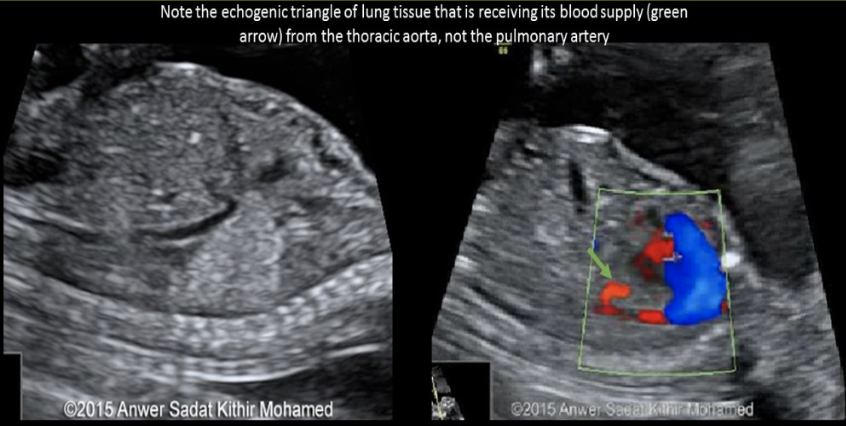

when evaluating a fetus w/alobar holoprosencephaly,

.

you identify a proboscis + a single midly enlarged, anechoic orbital cavity. what is the term for the ocular abn

a) cyclopia

b) epignathus

c) encephalocele

d) arhinia